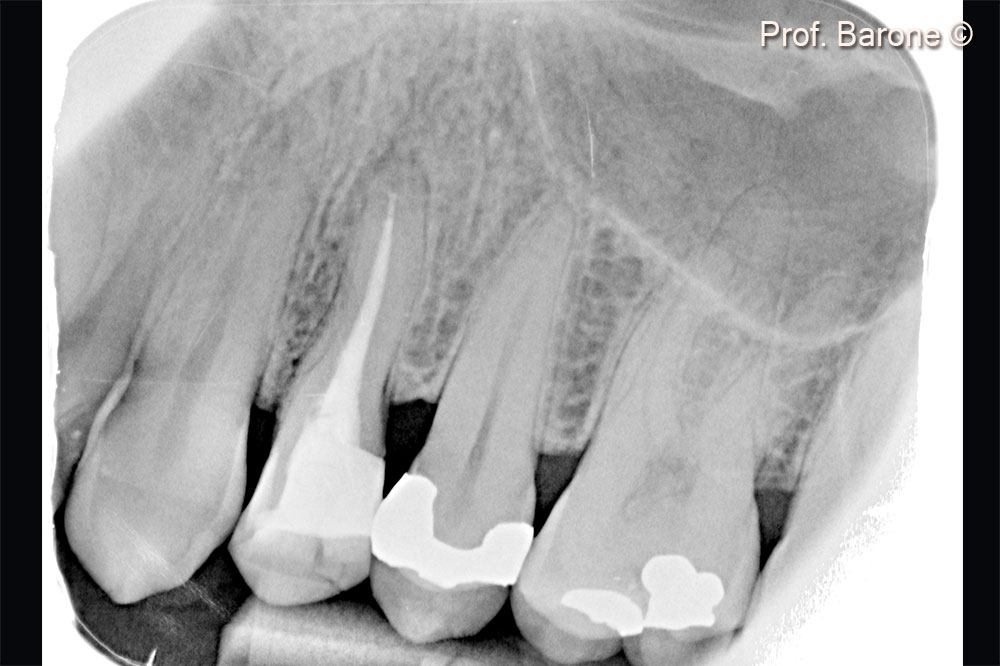

Pre-operative periapical radiograph